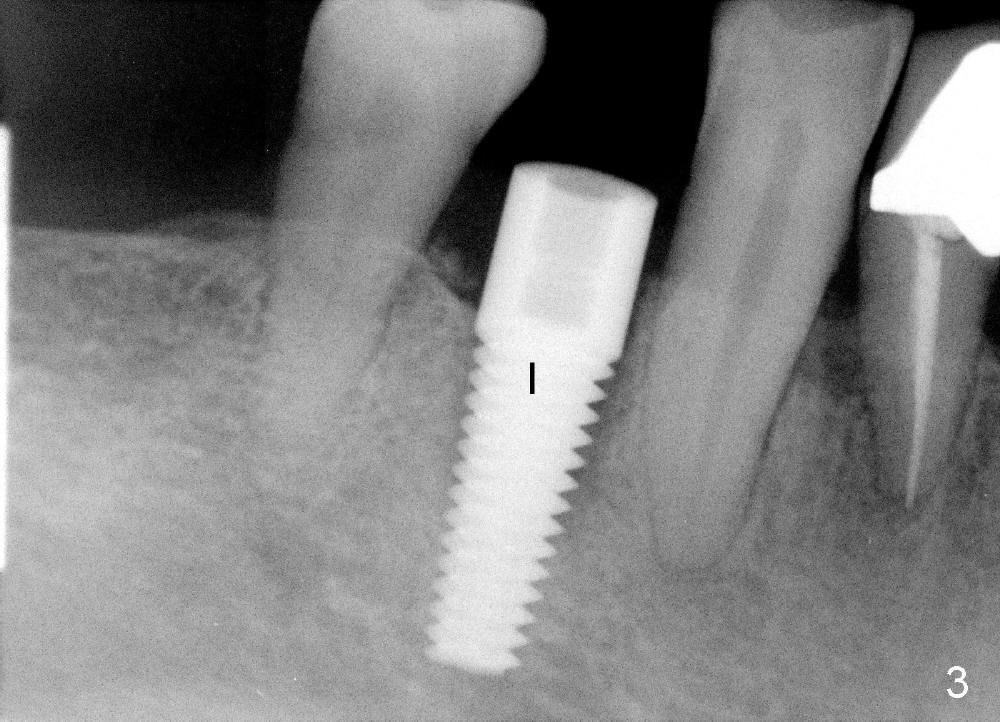

A 66-year-old man has poor dentition (Fig.1). Several teeth (x) including #28 need extraction and implants. The tooth #28 is extracted (Fig.2), followed by immediate implant (5x17 mm, Fig.3 I). There is more buccal gingival recession over the implant (Fig.4), which is less prominent 1.5 months postop (Fig.5). The definitive restoration is delivered less than 2 months postop (Fig.6), because of travel abroad. The patient agrees not to chew with the Emax crown. Five months later, he returns with chipped porcelain (Fig.7 arrowhead). It appears that immediate implant can survive early and over loading. More implants are necessary to share the masticatory loading. Since there is malocclusion, where to place implants appears to be critical (Model 3 30 4 5 6 7). There is no bone loss 4.5 years (Fig.8) or 5 years 8 months (Fig.9) post cementation.